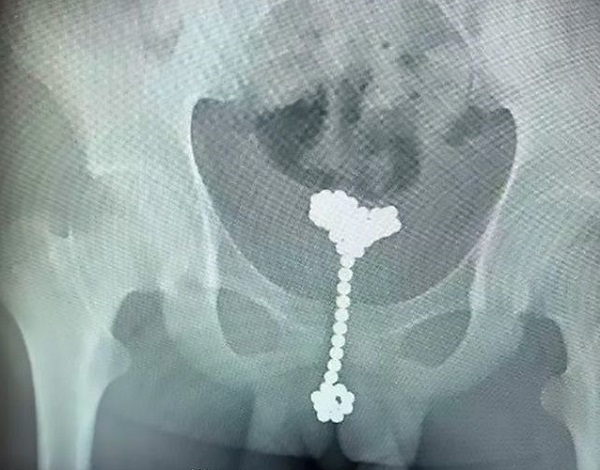

Những viên bi nằm trong cơ thể cậu bé một thời gian dài - Ảnh: The Sun |

The Sun đưa tin, bé trai 12 tuổi đến từ thành phố Vũ Hán, thủ phủ của tỉnh Hồ Bắc, Trung Quốc được đưa tới bệnh viện trong tình trạng đau bụng dữ dội.

Dù đã phát hiện ra vấn đề nhưng việc lấy các viên nam châm ra ngoài cũng không hề dễ dàng. Cuối cùng, các bác sĩ phải làm đầy bàng quang của bệnh nhân bằng cách bơm không khí vào, giúp dễ dàng xác định vị trí và dễ lấy các viên bi hơn. Biện pháp này cũng tỏ ra hiệu quả, giúp tránh việc phải phẫu thuật, gây tổn thương cho cơ thể cậu bé.

Bác sĩ tiết niệu Wang Jun cho biết các viên bi mắc kẹt trong cơ thể cậu bé "rất khó lấy" do đặc tính từ tính vốn có của nam châm.

"Chúng có xu hướng trượt ra khi chúng tôi cố gắng gắp bỏ hoặc kết dính với nhau, tạo thành một cụm hình quả bóng lớn", bác sĩ kể lại.

Hiện tại, các dị vật đã được lấy ra khỏi bàng quang của bệnh nhân. Dự kiến, cậu bé sẽ sớm hồi phục hoàn toàn.